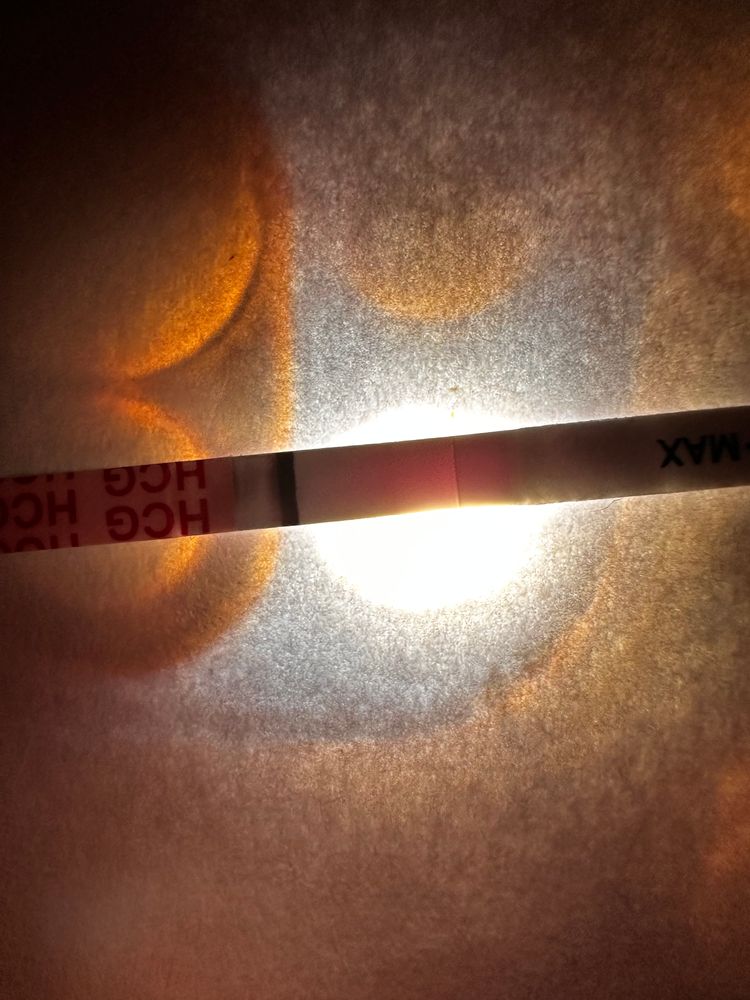

Девачки, почитала всех и короче пошла тесто манить , не могу уснуть теперь 😂😂😂😂 во что получилось напоминаю на 6 дпо

тест на о сегодняшний

Тест с верху старый 2 цикла назад

Тест с верху старый 2 цикла назад

Тест с верху старый 2 цикла назад

Тест с верху старый 2 цикла назад

Алина Горева, что-то есть, но мне кажется тест потек(

лучше переделать